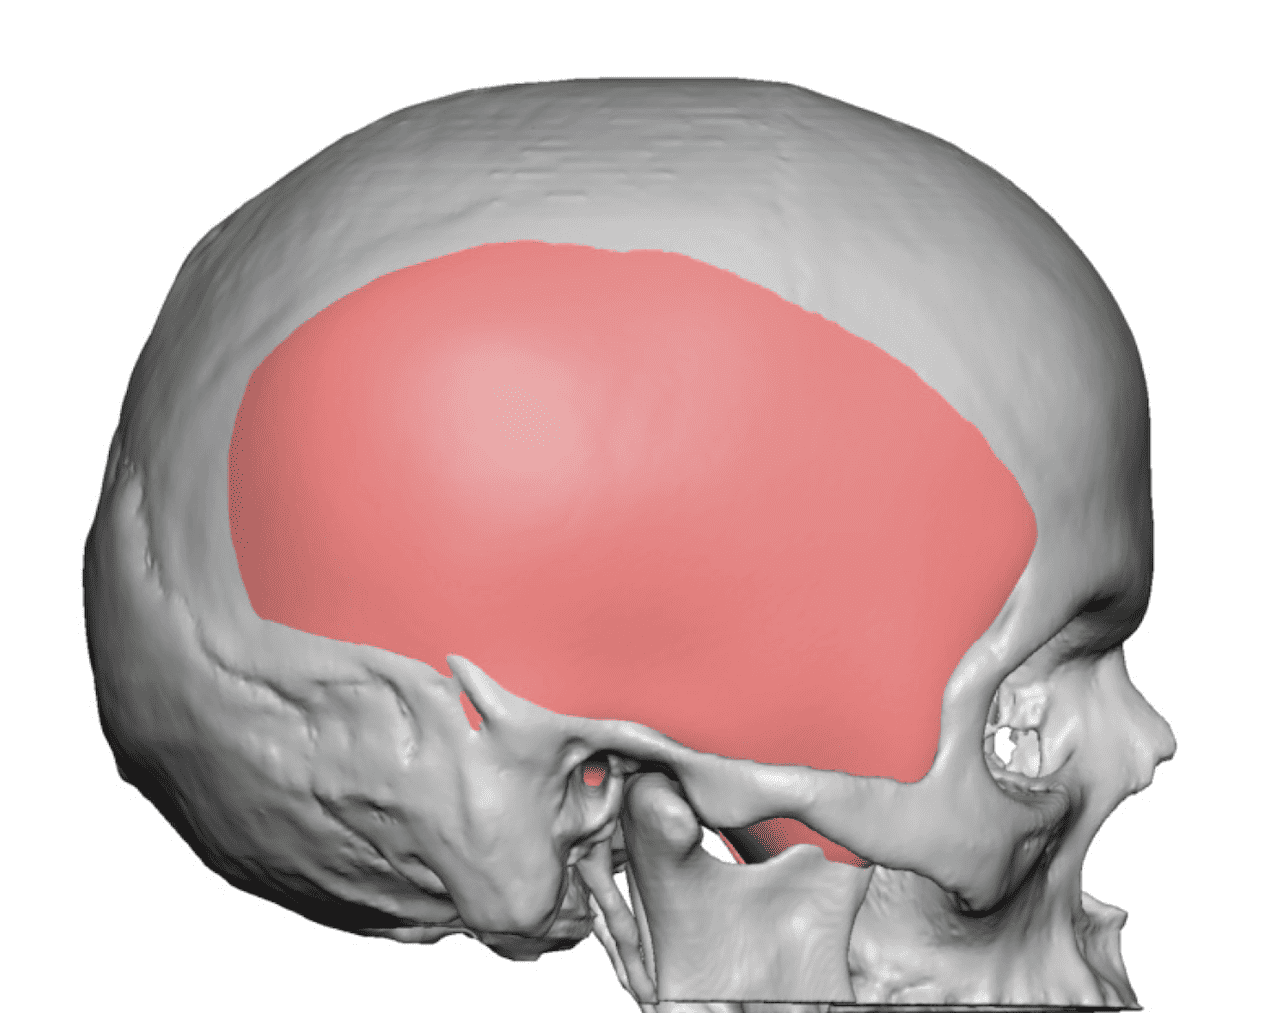

Desire for an improved head shape so that it looks rounder and not so peaked or sloped.

Placement of custom skull implant for parasagittal augmentation to create a rounder head shape. An example of what appears to be a high sagittal crest that is really low parasagittal skull areas.

Desire for an improved head shape so that it looks rounder and not so peaked or sloped.

Placement of custom skull implant for parasagittal augmentation to create a rounder head shape. An example of what appears to be a high sagittal crest that is really low parasagittal skull areas.